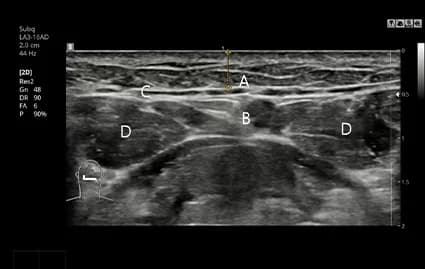

ถ่าย CT และอัลตราซาวด์ก่อนผ่าตัด

ใช้ผลตรวจ CT และอัลตราซาวด์เพื่อวิเคราะห์ตำแหน่งและขนาดอย่างละเอียด เพื่อดำเนินการผ่าตัดแบบเฉพาะบุคคลอย่างแม่นยำ